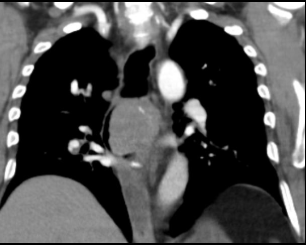

Aumento do tronco da artéria pulmonar

Estenose congenita da valva pulmonar.